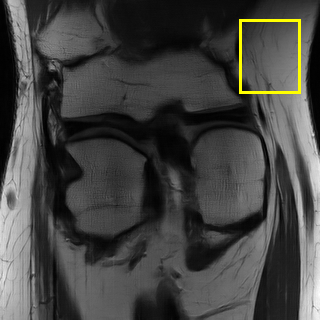

Edge preserving has always been a crucial concern in the design of reconstruction models. To improve the quality of reconstructed images and preserve image edges, some works suggested introducing edge priors in the original restoration problem to preserve image edges [4, 34]. However, they will suffer from complicated algorithm design and time-consuming training processes. Recently, some more efficient methods have been proposed to use edge maps as external guidance for image restoration. For example, Yang et al. [48] used off-the-shelf edge detectors to extract image edges from the degraded images. Fang et al. [12] predicted image edges by constructing an edge reconstruction network. Huang et al. [18] designed a novel dual discriminator GAN framework for solving fast multi-channel MRI, in which one GAN network is built for edge information enhancement. Inspired by these methods, we also consider introducing image edge prior as external guidance to MRI reconstruction since 1) image edges are prominent and distinguishable features in MRI (see Fig. 1), which can serve as a good guide to the model to recover high-frequency details; 2) the ground truth edges can be easily fetched via ordinary edge extraction operators, like Canny, Sobel, and Prewitt, which means that the edge maps can be learned in a data-driven manner. However, how to effectively utilize image edge priors to guide image reconstruction still remains a challenge. In some methods, edge information was simply concatenated with the input image and passed to the next stages. Though this is a simple way to utilize the edge priors, it may not give full play to the guiding role of the edge priors. Therefore, in this work, we want to explore a more efficient and effective mechanism to fully take advantage of image edge priors.

fastMRI is a large-scale MR dataset jointly established by Facebook AI Research and NYU Langone Health. It provides both knee and brain datasets for evaluation. In our work, we use the multi-coil knee dataset, which was acquired on three clinical 3T systems or one clinical 1.5T system using a 15-channel knee coil array. The dataset includes data from two pulse sequences, yielding coronal proton-density weighting with (PDFS) and without (PD) fat suppression. As is shown in Fig. 1, PD images usually contain more structural and prominent edge features than PDFS images, which suggests that it is more challenging to use edge guidance on PDFS datasets. Therefore, we explore the effectiveness of EAMRI on these two modalities. Following [13], for both PD and PDFS knee datasets, we separately filter out 227 volumes (8332 slices) for training and 24 volumes (1665 slices) for testing. The dataset is centrally cropped to .

In Table 2, we provide the quantitative results of all the models over three multi-coil datasets: Calgary [37], fastMRI PD [50], and fastMRI PDFS [50]. According to the table, we clearly observe that EAMRI achieves the best performance over all these datasets under both AF 4 and AF 6. For the T1-weighted images (Calgary) and the PD images (fastMRI PD), whose edge features are more prominent and structural (see Fig. 1), EAMRI can achieve high-performance gain when compared with the second-best model. For example, when the AF = 4, PSNR is boosted by 0.64 over Calgary, and 1.26 over fastMRI PD. On the other hand, for the PDFS images under AF 4, PSNR is boosted by 0.22 when comparing EAMRI with the second-best model. This is because PDFS images usually contain more broken edges, which is more challenging to use the edge guidance mechanism. Fortunately, our EAMRI can still achieve better results, thanks to its well-designed network structure and edge priors.